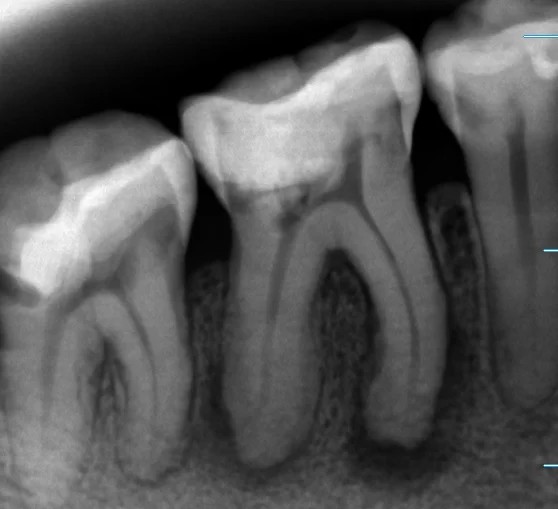

まずは術前です

「ほとんど全周」という広範囲に保険内の白い詰め物である「コンポジットレジン」が詰められています。 この治療は歯を削る量も少なくて済みますし、見た目も綺麗なのですが・・・

残念ながら今回は強度的に不可能なレベルを無理やり詰められてしまっていたようです。

詰められたコンポジットレジンが割れて中で大きく虫歯になっています。

そしてそのまま虫歯が神経に到達し根の先に膿が溜まってしまっているという状況です。